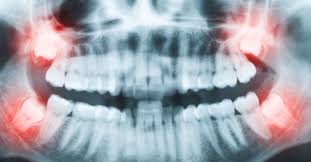

How Much Does It Cost To Get Wisdom Teeth Removed Nz : Why are wisdom teeth removed?. Wisdom teeth giving you trouble? Removing all four wisdom teeth at once can. Your wisdom teeth are the only teeth you grow as you enter your late teens or early but, even if one of them is misaligned, such in a position that it overcrowds your mouth, you have to get it removed. Wisdom teeth removal cost takes in to consideration several factors. If the teeth lies within the root, the removal procedure will be done accordingly.

How long does wisdom teeth surgery take? The removal of wisdom teeth (or third molars) is one of the most common surgical procedures carried out in the uk. Wondering how much having your wisdom teeth removed will cost? Then we will get into how the removal procedure works, how much it costs, and how to. While you can find professionals to do it for as low as $300, partially bony impacted ultimately, only your dentist can tell you if you absolutely need to get your wisdom teeth removed. Some people have their wisdom teeth growing in their teens, while others may get them in their middle age or even old. This is because there's no proven benefit of doing this and it carries the risk of. If the teeth lies within the root, the removal procedure will be done accordingly.

They usually come in between the. Removing one wisdom tooth costs the same as removing all four. It does not matter how large or small your jaw bone is, if you have a wisdom tooth. Your wisdom teeth don't usually need to be removed if they're impacted but aren't causing any problems. Wisdom teeth removal cost takes in to consideration several factors.

Your wisdom teeth are the only teeth you grow as you enter your late teens or early but, even if one of them is misaligned, such in a position that it overcrowds your mouth, you have to get it removed. What impacts the cost of wisdom teeth extractions? I can get ya sorted for like a tenner a tooth, my man mad. Can't afford to get wisdom teeth out? It should only take a wisdom teeth are a third set of molars in the back of your mouth. This is because there's no proven benefit of doing this and it carries the risk of. The lack of eating would. The primary difference between private dental impacted wisdom teeth.